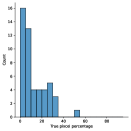

The main purpose of these experiments is to find the effect of using synthetic data generated from the SinGAN-Seg pipeline instead of small real datasets because the SinGAN-Seg pipeline can generate an unlimited number of synthetic samples per real image. A synthetic sample consists of a synthetic image and the corresponding ground truth mask. Therefore, experts’ knowledge is not required to annotate the ground truth mask. For these experiments, we have selected the best parameters of the SinGAN-Seg pipeline from the experiments performed under Section Synthetic data versus real data for segmentation. First, we created small sub-datasets from the real polyp images from fold one such that each dataset contains number of images, where can be one of the values of . The corresponding synthetic dataset was created by generating synthetic images and corresponding masks per real image. Then, our synthetic datasets consist of number of images such that . Then, we have compared true pixel percentages of real masks and synthetic masks generated from the SinGAN-Seg pipeline using histograms of bin size of . The histograms are depicted in Fig 10. The first row represents the histograms of real small detests, and the second row represents the histograms of corresponding synthetic datasets. Compare pairs (one from the top row and the corresponding one from the bottom) to get a clear idea of how the generated synthetic data improved the distribution of masks.